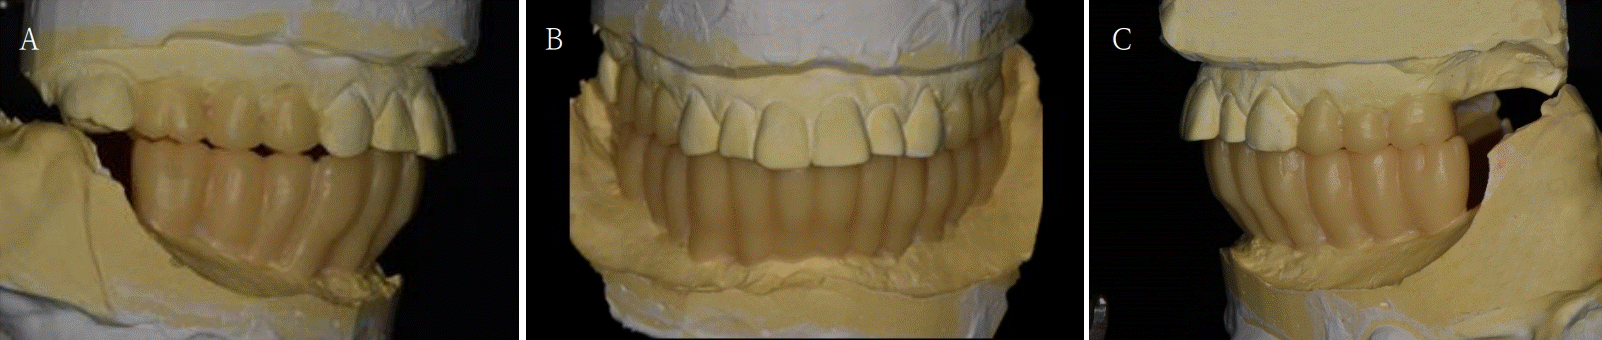

Fig. 4.

Ideal occlusal plane is developed with diagnostic wax up model. A. Right side view. B. Frontal view. C. Left side view.

본 증례는 44세 여환으로, 하악 의치가 계속 탈락하여 재제작을 원한다는 주소로 내원하였다. 상악은 고정성 수복물, 그리고 하악은 총의치를 착용 중이었고 하악 양측 구치부의 심한 골 흡수로 인해 유지력 소실로 불편감을 호소하였다. 3개월 전 하악 양측 견치를 발거한 이후로 하악 국소의치를 총의치로 전환하였고, 총의치는 구치부의 심한 교합면 마모와 의치의 후방부가 후구치 삼각 융기를 피개하지 않는 형태였다. 전신 병력으로는 지적장애 및 골관절염으로 약 2개월 간 약물 복용 중이었다. 상악 우측 제1대구치와 제2대구치, 제1소구치 그리고 제2소구치는 우식이 진행된 상태였고, 우측 제2소구치와 우측 제1대구치는 근관치료가 완료된 후 수복되지 않은 상태였다. 상악 좌측 제1소구치와 제2소구치, 그리고 제1대구치 수복물 하방으로 이차 우식이 진행된 상태였고, 전체적으로 교합평면이 균일하지 않은 형태였다(Figs. 1-3).상악 우측 구치부의 수복되지 않은 치아와 상악 좌측 보철물 하방의 이차 우식이 있는 치아는 모두 우식 제거가 필요하여 양측 구치부 각각 3개의 치아는 재수복을 결정하였고, 하악은 구치부의 심한 치조골 흡수로 인해 의치 사용은 불가할 것으로 판단하여 전방부에 임플란트를 식립하여 구치부는 캔틸레버 형태를 가지는 all-on-X 수복을 계획하였다. 의치의 수직고경에 맞춰 교합 평면을 균일하도록 하여 왁스업 시행하였고(Fig. 4), 이후 적절한 교합 수직 고경의 임시 의치를 제작하였다. 약 2개월의 적응기간을 거쳐 의치 적응도와 수직 교합 고경을 평가하였고 적절한 기능과 심미를 확인하였다. 상악 우측 제1소구치와 제2소구치, 제1대구치 그리고 상악 좌측 제1소구치와 제2소구치, 제1대구치는 우식을 제거한 다음, 임시 보철물로 재수복하여 적절한 교합 평면을 설정하였다(Fig. 5).환자가 적응한 임시 의치를 모델 스캔(Medit T710, Medit, Seoul, Korea)하여 프린팅용 레진(Graphy Tera Harz SG-100, Graphy, Seoul, Korea)을 이용하여 3D 프린팅하였고, 출력된 의치에 방사선 불투과성 레진(G-æenial Universal Flo, GC, Luzern, Swiss)을 부착하여 레진 마커를 형성하였다. 레진 마커를 부착한 프린팅 의치를 장착한 채로 콘빔 전산화 단층촬영(CBCT, R2 Studio Q, Megagen, Seoul, Korea)를 촬영하였다(Fig. 6). 촬영한 CBCT 데이터와 의치 스캔 파일을 중첩하여 CAD 소프트웨어(R2 Studio Q, Megagen, Seoul)를 통해 이상적인 임플란트 식립을 계획하였다. 전후방 거리를 연장하여 적절한 캔틸레버를 부여하기 위해 전방부에 3개의 임플란트를 식립하고, 양측 후방부에는 약 30도 경사진 임플란트를 식립하도록 계획하였다(Fig. 7).가이드는 상악의 자연 치열과 대합되는 의치 복제 형태의 상부 가이드, 그리고 가이드 핀이 존재하는 하부 가이드로 이루어지도록 디자인되었다(Fig. 8). 상부 가이드는 임시 의치의 스캔 데이터를 이용해 상부 가이드의 하부면과 하부 가이드의 상부면이 장착되어 구내에서 적합될 수 있도록 CAD 소프트웨어(Meshmixer, Autodesk, San Francisco, CA, USA) 상에서 디자인되었다. 임시 의치의 하부면과 하부가이드의 하부면을 치은과 중첩시켜 어버트먼트의 위치에 홀을 형성한 다음 3D 프린팅(Graphy Tera Harz SG-100, Graphy, Seoul, Korea) 하였다. 수술 당일 장착될 임시 보철물 또한 동일한 CAD 소프트웨어를 통해 제작하였다.수술 당일 이중 가이드를 구내에 장착하여 하부가이드를 고정 핀으로 고정시킨 후(Fig. 9), 계획된 위치에 임플란트 고정체를 식립하였다. 임플란트는 5개 모두 외부 연결형 고정체(AnyOne External, Megagen, Seoul, Korea)를 사용하였고, 식립 시 식립 토크는 모두 40N 이상, ISQ는 70이상으로 양호한 초기 고정력을 확보하였다(Fig. 10). 즉시 부하를 위해 기성 어버트먼트를 체결하였고, 임시 보철물을 장착하여 양측 소구치부에서의 균일한 교합을 확인하였다(Fig. 11).임플란트 주위 골과 치은의 회복을 위해 약 2달간 임시 보철물을 경과 관찰하였고, 이후 최종 보철을 위한 인상 채득을 시행하였다. 상하악 임시 보철물을 장착한 중심교합 상태에서 구내 스캔(Trios 4, 3 Shape, Copenhagen, Denmark)을 시행하여 악간 관계를 채득하였다(Fig. 12). 임시 보철물을 제거한 상태에서 하악의 전방부 3개의 임플란트에 scan body(Scan Abutment, Megagen, Seoul, Korea)를 연결하고, 양측 최후방 임플란트 2개에는 각각 Ti base multi-unit abutment(multi-angled abutment, Osstem, Seoul, South of Korea)를 30Ncm으로 체결한 후 multi scan body(TS Multi scanbody, Osstem, Seoul, Korea)를 연결하여 구내 스캔(Trios 4, 3Shape, Copenhagen, Denmark)을 시행하였다. 이후 스캔 바디를 연결하여 채득한 스캔 파일을 상하악 임시 보철물 상태에서 채득한 스캔 파일과 중첩하여 CAD 소프트웨어(exocad GmbH, Darmstadt, Germany)에서 최종 보철물을 디자인하였다(Fig. 13).최종 보철물은 양측 최후방 임플란트 고정체에 각각 Ti-base(TS multi Ti base, Osstem, Seoul, Korea)와 접착된 나사 유지형 단일 지르코니아 크라운으로, 지르코니아 블록(Zircen, Kuwotech, Gwangju, Korea)을 밀링하여 제작하였고, 치경부 하방으로 포세린으로 치은 형태를 부여하였다. 전방부 3개의 임플란트 고정체에는 맞춤형 지대주를 제작하여 30N으로 체결하였고, 양측 최후방 고정체는 20Ncm으로 체결한 후 레진 시멘트(Rely X U200; 3M ESPE, St. Paul, MN, USA)로 접착 시행하였다. 장착 후 중심교합시 양측의 제1대구치 부위에서 교합력이 적게 가해지도록 교합 조정 시행하였으며, 전방과 측방운동시에 임플란트 상호보호교합이 되도록 조정하였다. 또한 연결부 하방으로 치실을 통과시켜 치은 점막 사이 공간을 평가하였으며, 구강 위생 관리의 용이성을 확인하였다. 이후 1주, 1개월, 3개월 경과 관찰하였고, 환자는 저작이나 심미, 발음 등에서 만족해하였다(Figs. 14 and 15).